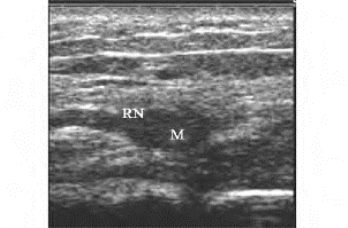

1.39.7七、其他骨、关节、肌腱、周围神经及软组织疾病